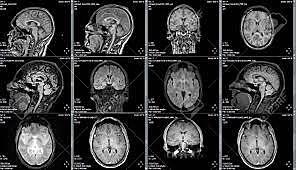

• Resonancia magnetica nuclear

Resonancia magnetica nuclear

Luego de la topografía axial computarizada Godfrey Houndsfield , creó un metodo de diagnóstico que eliminaba la radiación para el paciente.